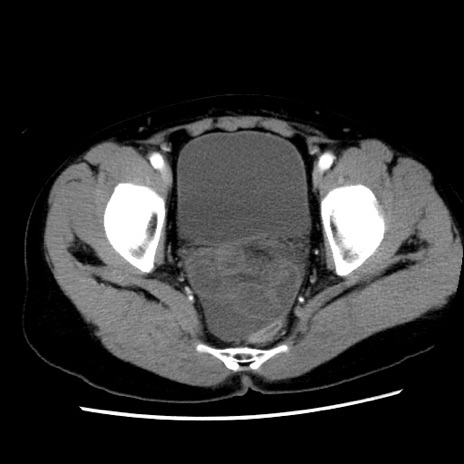

矢状断像

【症例】 50歳代女性

【主訴】 腹痛

【現病歴】前日生レバーを食べた。今朝に排便あり。 昼前に突然発症の腹痛を生じ、当院救急外来を受診した。

【既往歴】 子宮筋腫にてで子宮全摘後

【身体所見】 意識清明、腹部:平坦、軟、下腹部やや左を中心に圧痛・反跳痛あり、筋性防御あり

【データ】WBC 7800、CRP 0.07